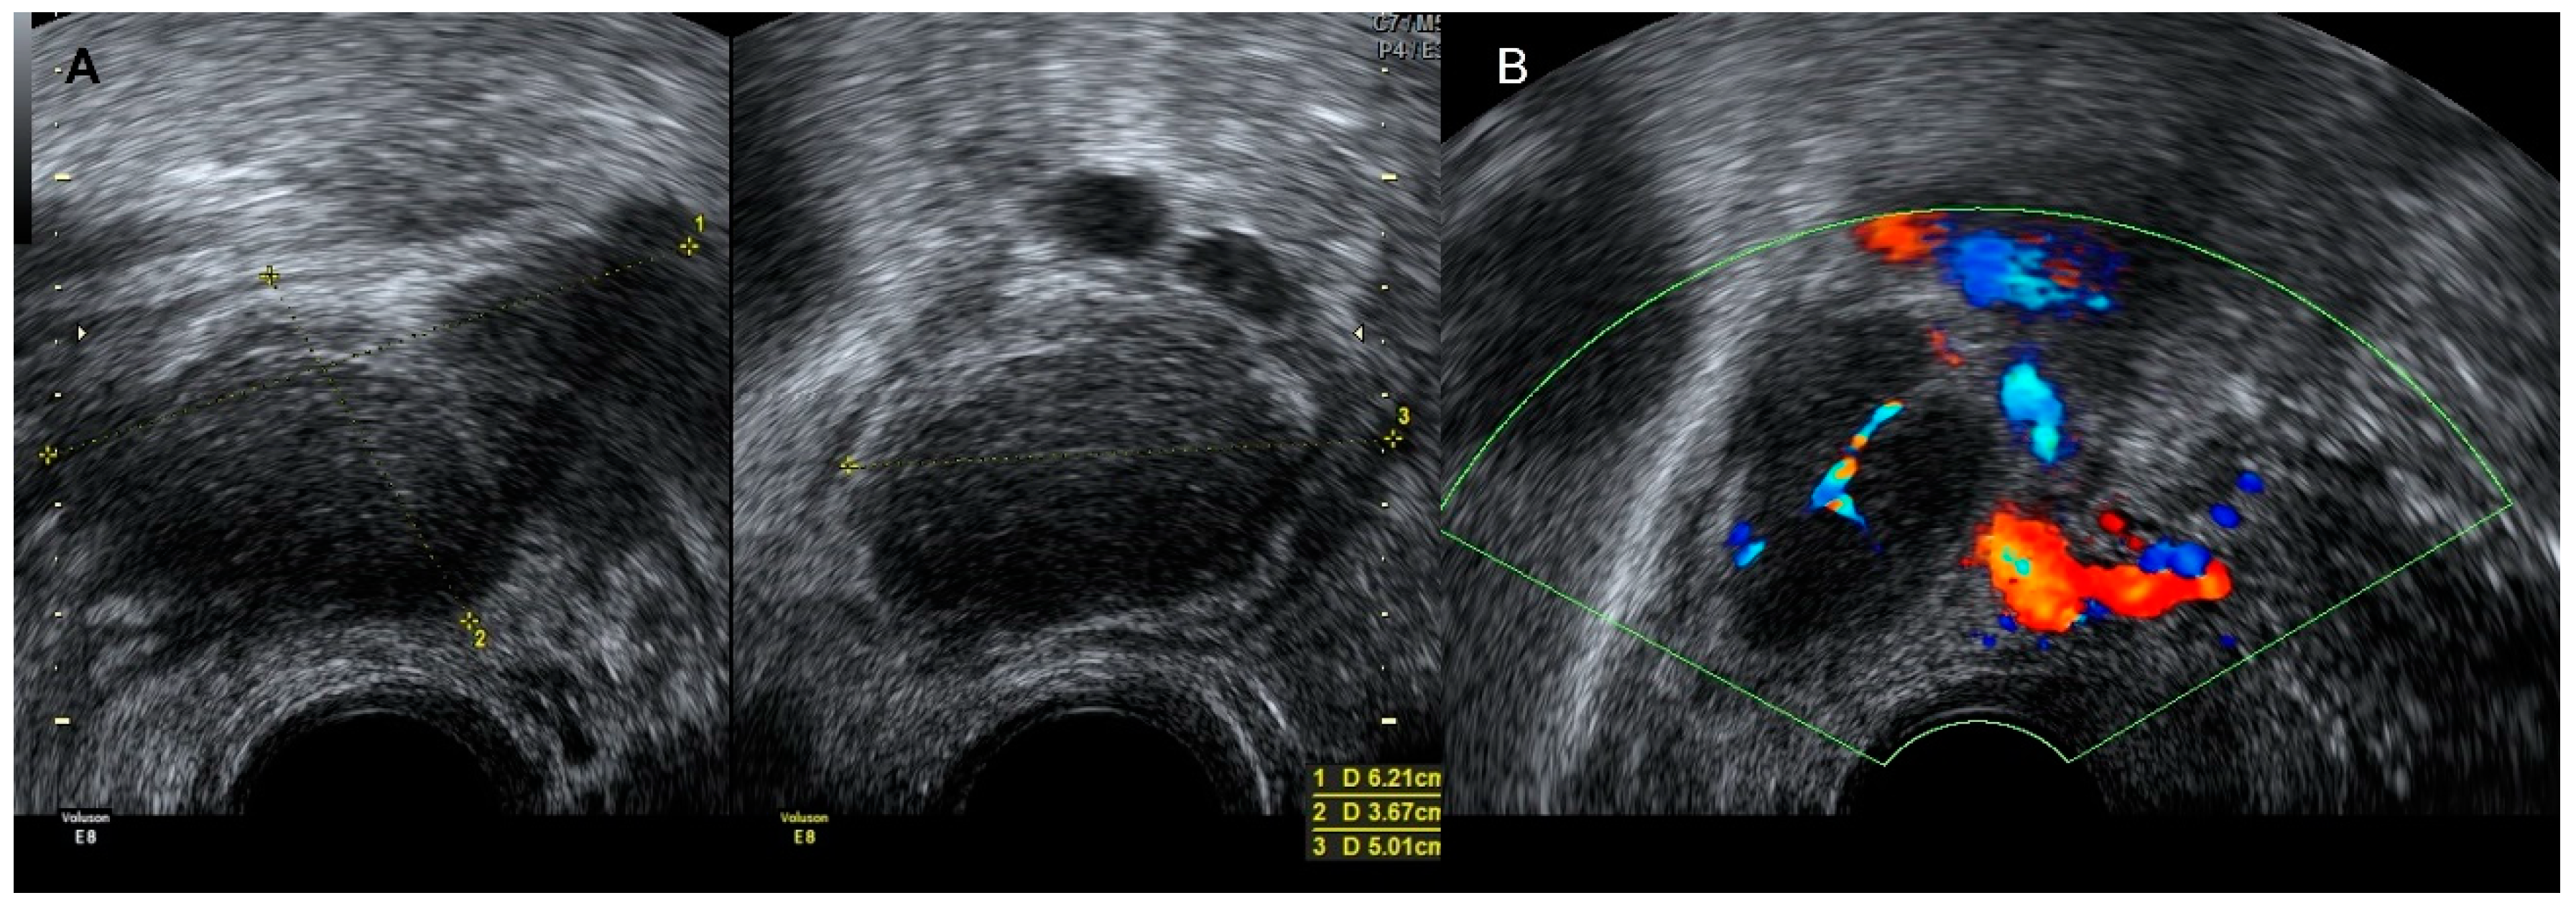

4.3. Aneurysm